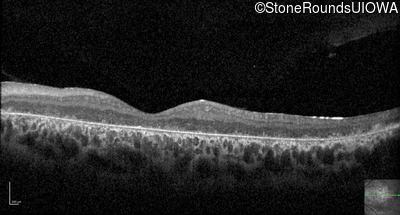

Optical Coherence Tomography - Right - 20/200 -3 sc

Exemplar / OCT Stack